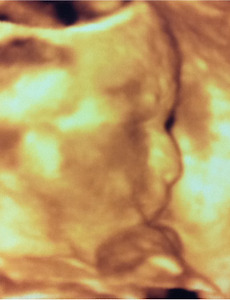

전체 글378 너 만의 명작을 그려라(마이클 린버그 저) 20대 때는 세상을 정의(定義)하는 것에 관심이 갔던 거 같습니다. 그때는 나 자신이 많이 혼란스러웠겠죠. (그때는 몰랐겠지만) 세상과 삶은 어떤 정의(定義)로 돌아가는지 배우고 싶어 읽었던 책인거 같습니다. 요즘을 두고 '철학의 부재의 시대'라고들 합니다. 이 책은 많은 위인들이 남긴 세상과 삶의 정의(定義)을 담고 있습니다. 책의 내용 중 슈바이처 박사의 글을 담아봅니다. 슈바이처는, “진리가 승리한다고 확신했던 사람이 지금은 더 이상 그런 확신을 가지고 있지 않다. 그는 인간을 믿었다. 그러나 지금은 아니다. 그는 선을 믿었다. 그러나 지금은 아니다. 그는 정의를 간절히 추구했다. 그러나 지금은 아니다. 그는 친절과 평화의 힘을 믿었다. 그러나 지금은 아니다. 그는 열정적인 사람이 될 수 있었다. .. 2011. 12. 16. 입체 초음파 사진을 찍었어요. (25주차 : 오늘 처음 긴장했습니다.^^;)[태아일기] 우리 아기의 초음파 사진입니다. 얼굴의 옆모습이죠. 지금 다니는 산부인과는 항상 입체 초음파 사진을 찍어주는 곳인데요. 처음 다니던 산부인과에 문제가 생겨 지금 다니는 산부인과로 옮겼는데요. 처음엔 산부인과를 옮기는 것에 집사람이 걱정 많이 했는데, 다행히 별 문제는 없더라고요. 옮기기를 잘 했단 생각도 들고요. 담당 선생님이 친절함과 확신의 믿음을 주시더라고요. 25주차인 이날은 병원 가면서 처음으로 긴장한 날이었습니다. 왜냐고요? 선생님께서 초음파 검사를 하는데 아기 손가락, 발가락 수 확인이랑 장기나 골격 등에 대한 상태를 말씀하시는 거예요. 다행히도 아무런 이상도 없어 다행이었는데, 처음 말씀하실 땐, 어! 이거 뭐지? 하면서 당황되고 긴장되더라고요. 혹시나 아기에게 잘못 있을까봐요. 그 때는 선.. 2011. 12. 16. 오~~~ 뭔가 형태가 나타나고 있습니다.(20주차 : 임신 기간의 중간 지점^^)[태아일기] 아래에 보이는 초음파 사진은 20주차 때 찍은 사진입니다. 20주차가 임신 기간의 중간 지점이라고 하더군요. 언제 키워서 언제 출산하나 했는데 벌써 반이나 지났네요. 이러다가 어~어~ 하다 출산하겠죠? 울 아기 빨리 보고 싶습니다. 그나저나 울 아이가 점점 사람같이 돼가고 있어요. 당연한 걸 알면서도 신기합니다. 그런데 사진에 얼굴이 안보이네요? 귀한 얼굴이니 자꾸 숨기나 봐요. 의사선생님의 말씀으론 외부자극으로부터 보호하기 위한 본능이랍니다. 점점 태동이 많아지나봐요. 집사람이 아이가 움직인다고 하면서 배를 만져보라고 하는데, 움직임이 미약해서 그런지 아직은 못 느끼겠더라고요. 그리고 우리 아기는 클래식을 좋아하나봐요. 집사람이 클래식을 들으면 마구 움직인다고 하네요. (대략 20주 이후부터는 외부의 .. 2011. 12. 16. Tools-4 [일러스트레이터,Illustrator] 오늘 알아 볼 툴들입니다. 1. Mesh Tool Mesh Tool은 오브젝트의 면을 그물망과 같이 만들어 줍니다. ② Mesh Tool을 선택해 사각형의 면을 클릭해 그물망 포인트를 만들어 줍니다. ③ 그물망 포인트를 이동하고 포인트의 컬러를 조정합니다. ④ 결과물입니다. 입체감이 생겼죠? (아니라고요? 제가 잘 못 해서 그래요.^^;) 2. Gradient Tool ① 그라데이션이 있는 박스입니다. ② 그라데이션 박스를 선택하면 그라데이션을 조정할 수 있는 바가 생깁니다. 그림은 조절바에 마우스 커서를 올린 모습입니다. ③ 조절바를 이용해 그라데이션의 컬러와 위치를 조정했습니다. 3. Eyedropper Tool 보통 스포이드 툴이라고도 하는데, 오브젝트A에 오브젝트B와 같은 성격을 부여할 때 쓰입니.. 2011. 12. 15. Tools-3 [일러스트레이터,Illustrator] 이번 페이지에서 알아볼 툴들입니다.툴들을 설명해보니 그동안 설명 드렸던 메뉴에 비해 설명이 수월하네요. 언어로 실행되는 명령어와 나의 손을 움직이는 모션적 툴의 차이점일까요? 아니면 툴의 아이콘을 직관적으로 잘 만들어서 일까요? 우리의 행동 양식을 이용해 만들어진 직관적 프로그램 툴은 다가가기 참 쉬운 거 같습니다. 1. Rotate Tool 오브젝트를 회전시킵니다. - Rotate Tool 아이콘을 더블클릭하면 아래와 같은 조절창이 열리고, 회전할 각도의 수치를 입력해 오브젝트를 회전시킬 수 있습니다. 2. Reflect Tool 오브젝트를 반전시킵니다. 3. Scale Tool 오브젝트를 확대·축소시킵니다. - Scale Tool 아이콘을 더블클릭하면 아래와 같은 조절창이 열립니다. 4. Shear .. 2011. 12. 14. 한권으로 읽는 드러커 100년의 철학(피터 드러커 저) 언제부턴가 책을 볼 때면 밑줄을 치곤합니다. 그리고 컴퓨터에 타자를 처 보관하곤 했습니다. 그 글들을 올려봅니다. 저작권으로 문제가 생기진 않겠지요? 괜찮은 책이니 밑줄처서 블로그에까지 올리겠죠? 구입해 읽어보세요~ (← 혹시 문제 생길까봐...ㅋㅋㅋ) 혹시 저작권에 문제가 있다면 메일 남겨주세요. 성공의 열쇠는 책임이다. 책임 있는 존재가 되는 것은 진지하게 일에 몰두하고, 자신이 성장해야 할 필요성을 인식하는 것이다. 중요한 임무를 맡게 되면 스스로를 중요하다고 느낀다. 자기개발이란 능력을 쌓는 것만이 아니라 인간으로서 상장해 나가는 것이다. 책임에 초점을 둠으로써 보다 큰 자신을 발견하게 된다. 성과를 올리는 사람과 그렇지 못하는 사람의 차이는 재능이 아니다. 몇 가지 습관적인 자세와 기초적인 방법.. 2011. 12. 12. 한국의 이공계는 글쓰기가 두렵다.(임재춘 저) 언제부턴가 책을 볼 때면 밑줄을 치곤합니다. 그리고 컴퓨터에 타자를 처 보관하곤 했습니다. 그 글들을 올려봅니다. 저작권으로 문제가 생기진 않겠지요? 괜찮은 책이니 밑줄처서 블로그에까지 올리겠죠? 구입해 읽어보세요~ (← 혹시 문제 생길까봐...ㅋㅋㅋ) 혹시 저작권에 문제가 있다면 메일 남겨주세요. 블로그를 쓰게 되면서 제게 생긴 변화가 두가지 있습니다. 그 전 같으면 “무심히 넘어갔을 것들에 대한 관심”과 “글 쓰는 법”입니다. 이 책은 어느 동생에게서 들어 알게 된 책인데, 제가 블로그를 쓰지 않았다면 만나지 못했을 책일 겁니다. ‘알고 있다’라는 말은 다시 한 번 되새겨 보자. 진정으로 알고 있다는 것은 다른 사람들에게 자신의 논리를 펴서 이해시킬 수 있고 설득할 수 있다는 것을 의미한다. 아마추어.. 2011. 12. 12. 프리젠테이션 잰(가르 레이놀즈 저) 언제부턴가 책을 볼 때면 밑줄을 치곤합니다. 그리고 컴퓨터에 타자를 처 보관하곤 했습니다. 그 글들을 올려봅니다. 저작권으로 문제가 생기진 않겠지요? 괜찮은 책이니 밑줄처서 블로그에까지 올리겠죠? 구입해 읽어보세요~ (← 혹시 문제 생길까봐...ㅋㅋㅋ) 혹시 저작권에 문제가 있다면 메일 남겨주세요. 컨퍼런스 강연의 보조 자료로서 ‘시각 자료’는 얼마나 사용되고 있는가? “말보다 기억에 오래 남는 것이 시각 자료다. 하지만 여전히 대부분 슬라이드에 글머리 기호가 가장 많이 쓰이며 시각 자료는 거의 사용하지 않는다. 같은 내용이 글과 음성으로 동시에 주어지면 정보 처리가 훨씬 어려워진다. 차라리 발표자가 입을 다물고 청중들이 화면상의 글을 스스로 읽게 하는 편이 더 나을지도 모른다. 준비 단계에서는 우선 마.. 2011. 12. 12. 슬랙(톰 드마르코 저) 언제부턴가 책을 볼 때면 밑줄을 치곤합니다. 그리고 컴퓨터에 타자를 처 보관하곤 했습니다. 그 글들을 올려봅니다. 저작권으로 문제가 생기진 않겠지요? 괜찮은 책이니 밑줄처서 블로그에까지 올리겠죠? 구독해 읽어보세요~ (← 혹시 문제 생길까봐...ㅋㅋㅋ) 혹시 저작권에 문제가 있다면 메일 남겨주세요. 건강한 지식 기업은 직원들을 오랫동안 보유하는 능력이 뛰어나다. 도메인 지식을 올바르게 이해하는 방법은 그러한 지식들을 마치 기업의 금융 자산처럼 생각하고 직원들에게 기업이 투자한 것으로 간주하는 것이다. 만약 여러분이 인적 자본의 가치에 대해 엄격한 회계 처리를 한다면, 한 사람이 조직을 떠날 때마다 엄청난 손실이 발생했다고 처리할 수 밖에 없을 것이다. 만약 시장이 이미 포화 상태에 있거나 또는 거의 포화.. 2011. 12. 12. 마켓 3.0(필립 코틀러 저) 언제부턴가 책을 볼 때면 밑줄을 치곤합니다. 그리고 컴퓨터에 타자를 처 보관하곤 했습니다. 그 글들을 올려봅니다. 저작권으로 문제가 생기진 않겠지요? 괜찮은 책이니 밑줄처서 블로그에까지 올리겠죠? 구독해 읽어보세요~ (← 혹시 문제 생길까봐...ㅋㅋㅋ) 혹시 저작권에 문제가 있다면 메일 남겨주세요. 마케팅? 경제학? 경영학? 저 이런거 잘 모릅니다. 하지만 관심은 많습니다. 재미있기도 하고요. 이 책 무척 재미있어요. 마케팅, 경제, 경영에 대한 책도 재미있을 수 있습니다.ㅋㅋㅋ 관심만 있다면요. IBM은 직원들에게 자신의 블로그를 만들어 특정한 지침을 거스르지 않는 한도 내에서 회사에 대한 의견을 자유롭게 교환하도록 장려하고 있다. GE의 경우 트윗 팀을 조직해 일단의 젊은 직원들로 하여금 나이 든 직.. 2011. 12. 12. the one page proposal(패트릭 G. 라일리 저) 언제부턴가 책을 볼 때면 밑줄을 치곤합니다. 그리고 컴퓨터에 타자를 처 보관하곤 했습니다. 그 글들을 올려봅니다. 저작권으로 문제가 생기진 않겠지요? 괜찮은 책이니 밑줄처서 블로그에까지 올리겠죠? 구독해 읽어보세요~ (← 혹시 문제 생길까봐...ㅋㅋㅋ) 혹시 저작권에 문제가 있다면 메일 남겨주세요 기획서 쓸 일도 없는 제가 왜 이런 책에 관심을 가졌었는지 오래전이라 기억에 없지만, 많은 것을 얻었던 책입니다. 꼭 읽어보시길 강력 추천합니다. 기획서의 형식은 제목, 부제, 목표, 2차 목표, 논리적 근거, 재정, 현재 상태, 실행 등의 8개 부문으로 나뉘다. 오히려 완벽한 사업 기획서는 서류를 읽기도 전에 그들을 좌절시키는데, 영어 실력이 뒷받침되지 않아서일 수도 있고 미국 스타일의 차트나 그래프. 기술적.. 2011. 12. 12. 집사람이 받은 생일 선물 집사람이 생일 선물을 받았습니다. 아직 1달은 남았는데 벌써 선물을 받았네요. 아는(저도 아는) 언니랑 간송미술관 갔다가 책 이야기를 했는데, 거기서 언니가 필(feel) 받아 선물하겠다고 했었다네요. 그 언니는 그냥 기분으로 말했다해도 실천으로 잘 옮기시는 분이거든요. 책을 네권이나 선물 받으니 부자가 된거 같아요. 선물 받은 책들입니다. 요즘 제가 읽는 책들과는 분위기가 다른, 차가운 머리가 아닌 따듯한 가슴으로 읽는 책들이네요. 1. 무량수전 배흘림기둥에 기대서서 : 언니가 추천했다는 책입니다. 꼭 봐야겠어요. 2. 간송 전형필 : 간송미술관을 만드신 분의 책이라네요. 3. 어린 왕자 : 이 책으로 차가워지고 있는 가슴을 덥여봐야겠습니다. 4. 윤미네 집(윤미 태어나서 시집가던 날까지) : 아빠가 .. 2011. 11. 25. 무자각한 악의 "무자각한 수동적 생각과 행동이 악의를 만든다"는 비판을 담은 대화입니다. (애니메이션 "건담 더블오" 중에서) 2011. 11. 9. 디자인 하지 않는 디자이너(나가오카 겐메이) 언제부턴가 책을 볼 때면 밑줄을 치곤합니다. 그리고 컴퓨터에 타자를 처 보관하곤 했습니다. 그 글들을 올려봅니다. 저작권으로 문제가 생기진 않겠지요? 괜찮은 책이니 밑줄처서 블로그에까지 올리겠죠? 구독해 읽어보세요~ 브랜드라는 것은 당연한 말이지만 마크만을 의미하지는 않는다. 그리고 또한 브랜드라는 것은 ‘브랜드를 만든다.’ 는 의식이 없으면 절대로 만들어지지 않는다. 적어도 나는 그렇게 생각한다. ‘브랜드를 만든다.’는 것은 세상에서 흔히 쓰는 느낌으로 ‘하나의 브랜드를 목표로 하여 만드는 행위’는 아니다. ‘내가 하고 있는 일이 바로 브랜드’라고 의식하며 그것을 철저하게 만드는 의식. 분명 그런 의식을 가지고 수년, 수십 년 동안 그것을 반접하는 것을 손님이 인정했을 때, 축하할 만한 브랜드가 되는 .. 2011. 11. 7. 게으름에 대한 찬양(버트런드 러셀) 언제부턴가 책을 볼 때면 밑줄을 치곤합니다. 그리고 컴퓨터에 타자를 처 보관하곤 했습니다. 그 글들을 올려봅니다. 저작권으로 문제가 생기진 않겠지요? 괜찮은 책이니 밑줄처서 블로그에까지 올리겠죠? 구독해 읽어보세요~ 일이란 무엇인가? 일에는 두 가지가 있다. 먼저 지표면 혹은 지표면 가까이 놓인 물질을 다른 물질과 자리를 바꿔 놓는 일이다. 또 하나는 타인들에게 그런 일을 하도록 시키는 일이다. 4시간 노동으로 생활필수품과 기초 편의재를 확보하는 한편, 남는 시간은 스스로 알아서 적절한 곳에 사용하도록 되어져야 한다는 뜻이다. 현명하게 더 많은 교육이 이루어지고 그 교육의 목표에 여가를 현명하게 사용하는 데 필요한 안목을 제공하는 항목이 들어 있어야 한다는 것은 어느 사회에서나 필수적이다. 도시 사람들의.. 2011. 11. 5. 물통의 법칙 (혼자만 잘 살믄 무슨 재민겨) 물통의 법칙이란 게 있어요. 옛날에는 요사이 시장에서 파는 명란통 같은 물통을 나무로 만들었습니다. 판자를 여러 쪽 모아 통을 짜는데 높고 낮은 판자로 통을 짰다고 합시다. 물은 가장 낮은 판자 높이밖에 차지 않아요. 지금 농민들은 농사짓는 일은 아주 열심히 합니다. 겨울에 하우스까지 만들어 죽자 살자 일해요. 그래서 한쪽 판자는 굉장히 높아요. 한편 스스로와 세상을 만드는 일에는 무관심해서 다른 쪽 판자는 아주 낮아요. 새빠지게 물을 부어 봤자 물은 낮은 판자까지만 차지 절대로 더 높이 올라가지 않지요. 그 차가 심할수록 좌절감은 크고 한은 사무칩니다. 전우익 님의 중에서 앞만 보고 달리는 거 좋습니다. 하지만, 가끔 주변도 봐주세요. 그러면 주변의 새로운 것에 즐거움을 느끼기도하고, 내 주변의 모르던.. 2011. 11. 2. Tools-2 [일러스트레이터,Illustrator] 이번 페이지에서 알아볼 툴들입니다. 팝업창에 가려졌던 툴까지 같이 보니 꽤 많네요. 1. Pen Tool 선을 그릴 때 쓰입니다. 선의 시작점과 끝점이 만나면 닫힌 선이 됩니다. 2. Add Anchor Point Tool 오브젝트에 점을 추가 시켜줍니다. 3. Delete Anchor Point Tool 오브젝트에 점을 삭제 시켜줍니다. 4. Convert Anchor Point Tool 중간에 위치하는 점을 수정할 수 있습니다. 5. Type Tool 글자를 입력할 수 있습니다. 6. Area Type Tool 임의의 오브젝트 안에 글자를 입력할 수 있습니다. 7. Type on a Path Tool 선을 따라 흐르는 글자 만들 수 있습니다. 8. Vertical Type Tool 글자 세로로 쓸 수.. 2011. 10. 31. Tools-1 [일러스트레이터,Illustrator] 드디어 힘들었던 ‘메뉴의 명령어’ 설명이 끝나고 툴 설명으로 넘어왔습니다. 오늘부터 몇 페이지는 Tool에 대한 설명입니다. Tool은 도구란 뜻이죠? Adobe Illustrator CS5는 무척 다양한 도구를 준비하고 있습니다. 위의 그림을 보니 무척 다양한 도구들이 있죠? 각각의 도구들은 용도를 직관적으로 알수 있게 아이콘으로 돼있습니다. 위부분의 Tool부터 설명하겠습니다. 그전에 Tool bar의 형태에 대해 잠깐 알아볼게요. 1. Selection Tool 클릭 또는 드레그해서 오브젝트를 선택할 수 있습니다. 보통 선택할 때는 이 툴을 많이 사용합니다.선택하면 오브젝트가 위와 같은 모습을 보입니다. 2. Direct Selection Tool 오브젝트의 일부분인 점이나 선을 선택할 때 주로 쓰.. 2011. 10. 29. 이전 1 ··· 15 16 17 18 19 20 21 다음 반응형